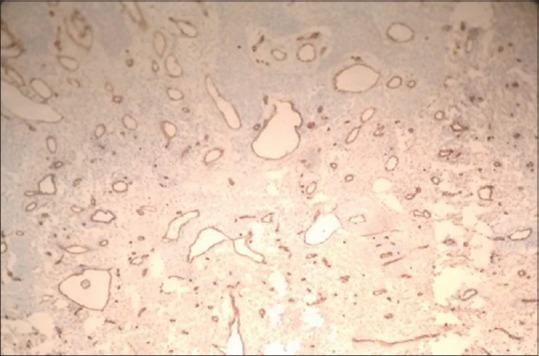

The angiomyxomas are rarely reported in the head and neck region; this paper entails a case of aggressive angiomyxoma presenting as a growth in the maxillary anterior alveolar mucosa and lip region for 1 year, which was accurately identified and treated successfully by surgical excision. An attempt has been made to highlight the clinical and pathologic stand out features of this tumor with intricate emphasis, alongside a literary review.

血管黏液瘤在头颈部区域鲜有报道;本文报道了1例侵袭性血管黏液瘤,该肿瘤表现为上颌前牙槽黏膜和唇部肿物,病程1年,经手术切除得以准确诊断并成功治疗。本文在进行文献回顾的同时,着重强调了该肿瘤的临床和病理突出特征。